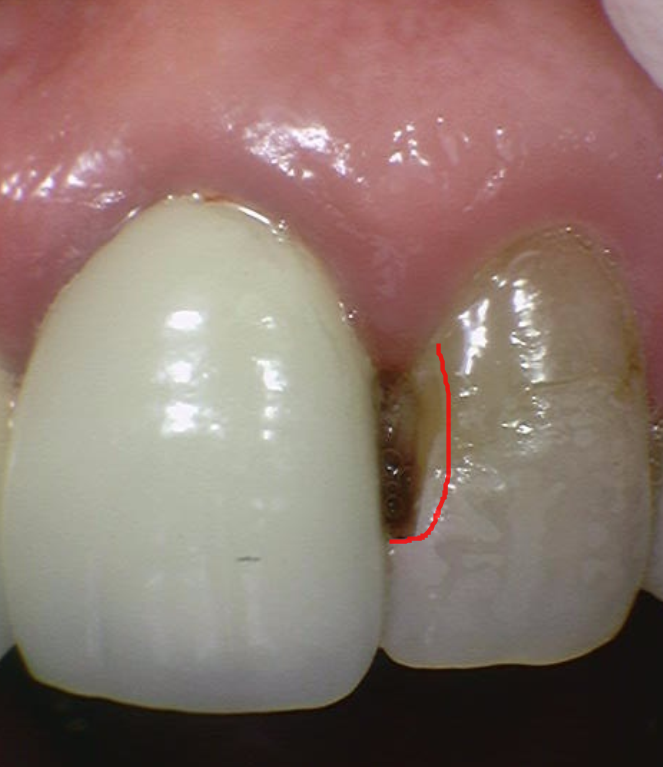

실제 구강을 살펴보았습니다.

231127

해당하는 치아에 치태도 많이 붙어있고

구멍도 나 있는 상태였습니다.

충치를 제거하고 치료를 해줘야하는데..

우선 충치를 제거 후 범위를 살펴보기로 하였는데요~

치아 뒤쪽에 까맣게 비춰보이는 부위가 충치입니다.

조심스럽게 제거를 해보겠습니다~